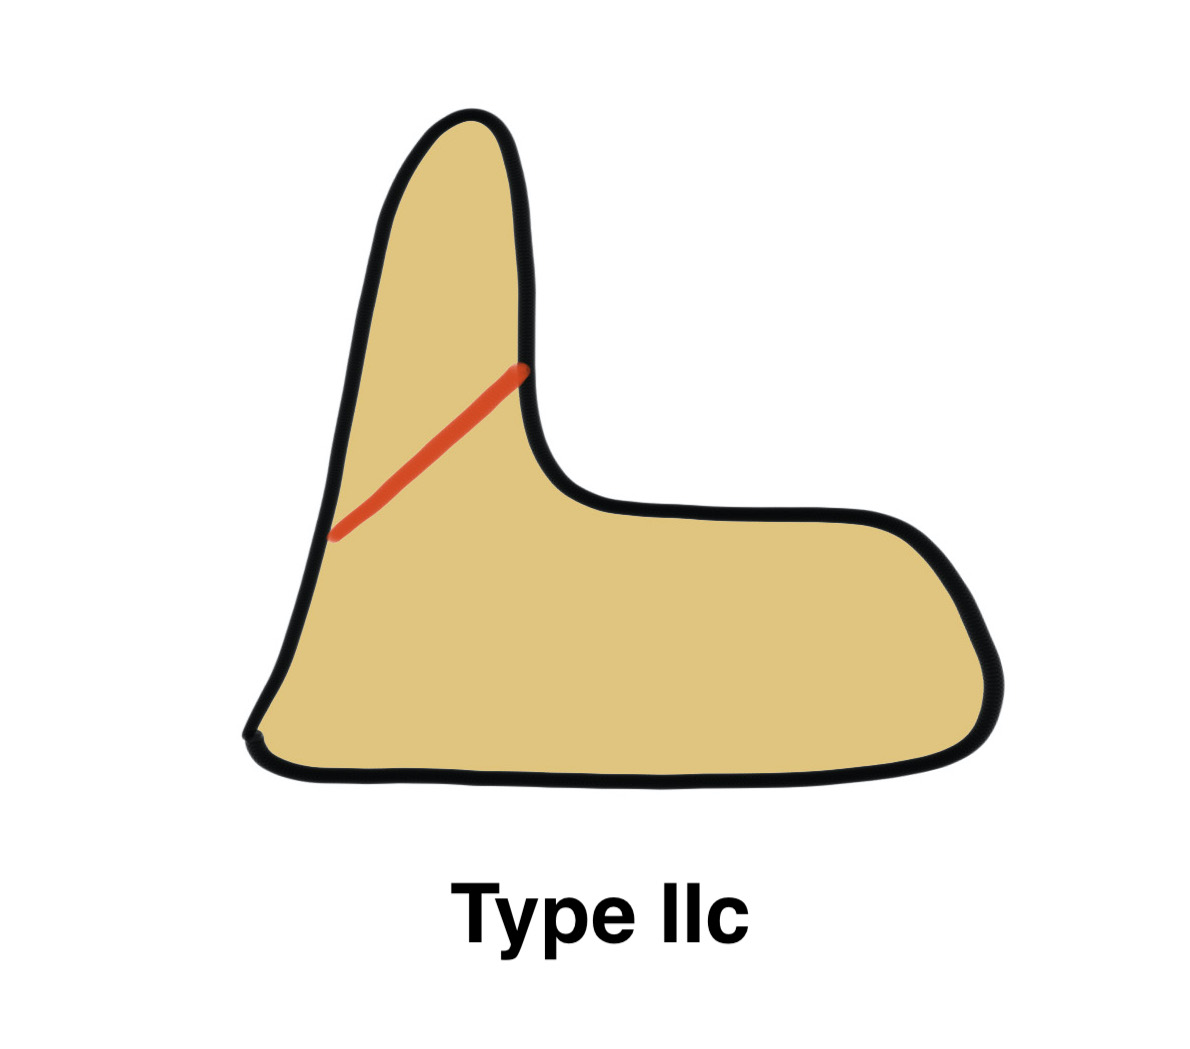

Grauer classification of Type II

| Type | Definition | Management |

| Type IIa |

Non or mimimally displaced No comminution |

Non operative treatment |

| Type IIb |

Displaced Fracture line anteror-superior to postero-inferior |

Potentially suitable for anterior odontoid screw |

| Type IIIc |

Displaced Fracture line antero-inferior to posteror-superior Significant comminution |

No suitable for screw Posterior fixation / fusion |